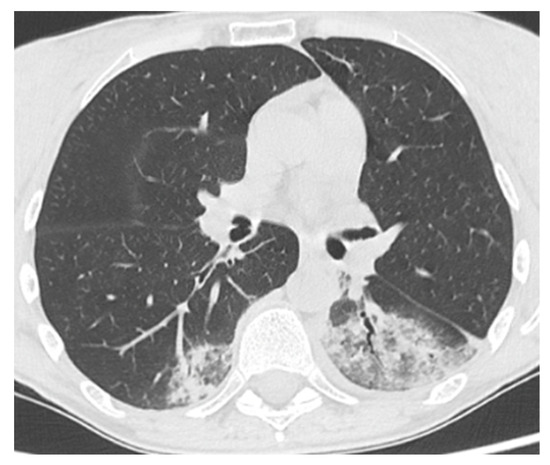

| Comorbidity | RA | Splenomegaly, bronchiectasis; recurrent viral infections | Hypertrophic cardiomyopathy; AF; CKD secondary to nephrolithiasis. C | Bronchiectasis; COPD; EBV-related NHL | GLILD; Bronchiectasis; colonization Aspergillus; Sjogren syndrome; CKD |

| Severity according to WHO classification | moderate | moderate | severe | severe | moderate |

| SARS-CoV-2 related pneumonia | yes | yes | yes | yes | no |

| O2 supplementation therapy needed | LFNC | LFNC | HFNC | HFNC | LFNC |